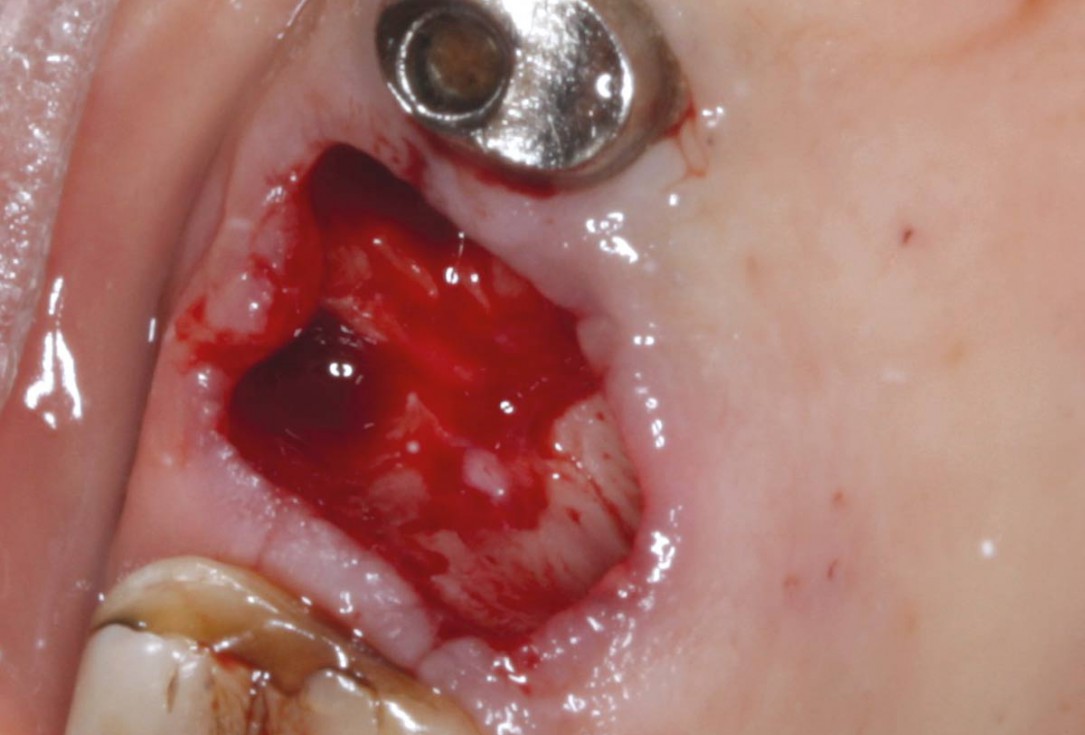

02/07 - Situation after tooth extraction.Socket preservation with permamem® - Dr. M. Turco